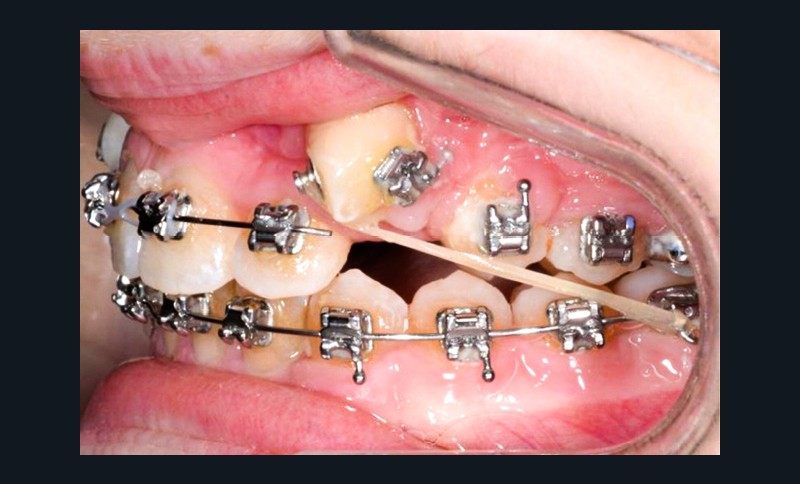

Trois jours plus tard, des bras en TMA .017 x .025 habillés d’une gaine de protection avec omega au contact des tubes des premières molaires et dont l’extrémité mésiale forme une boucle sont ligaturés aux dispositifs collés de traction.

Les maillons de la chaînette du dispositif de traction sont sectionnés progressivement de manière bilatérale à chaque rendez-vous à mesure que les canines sont déplacées en direction vestibulaire et le bras TMA est systématiquement religaturé au premier maillon transmuqueux avec une ligature métallique .010. L’ensemble est sécurisé par une goutte de composite fluide photopolymérisé.